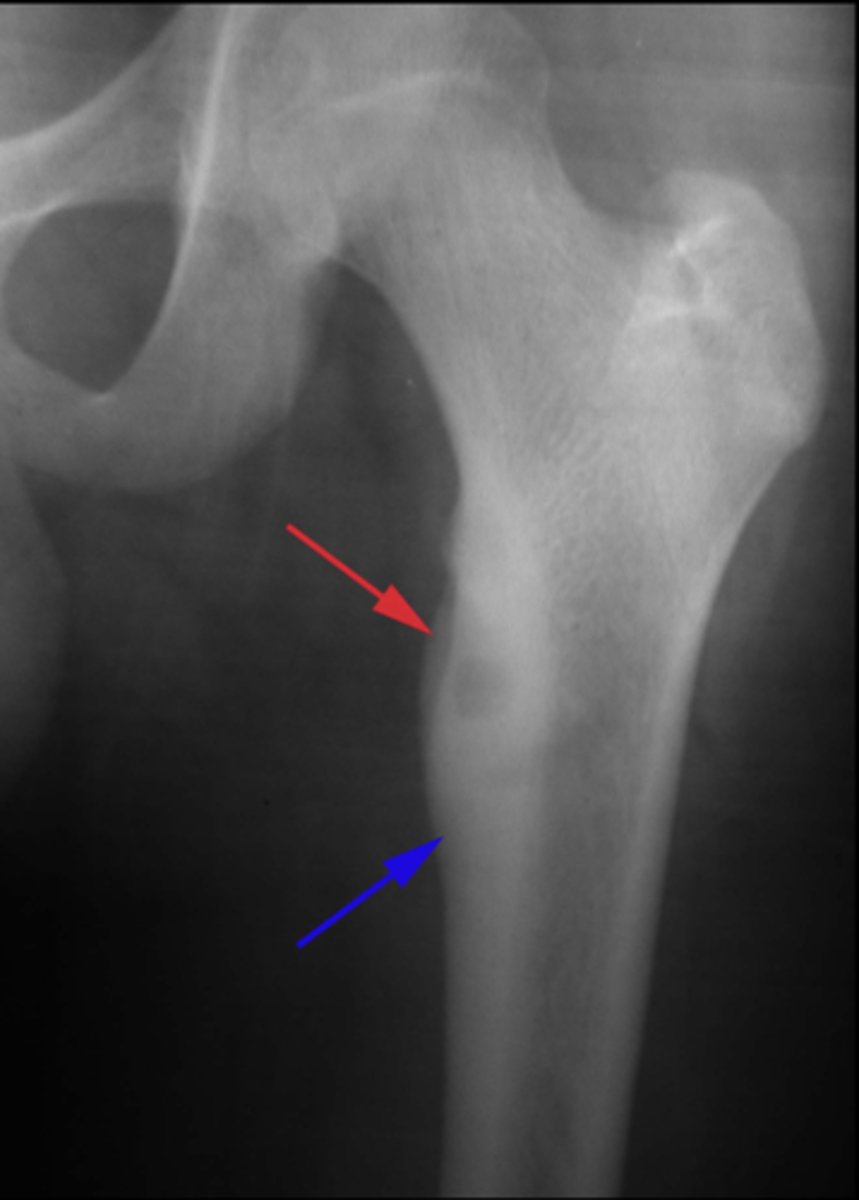

6

New cards

Solitary osteochondroma

- Most common benign skeletal growth or tumor

- 50% of all benign bone tumors

- 10-15% of all primary bone tumors

- 75% <20 y.o.

- M:F, 2:1

- Malignant transformation <1%

<p>- Most common benign skeletal growth or tumor</p><p>- 50% of all benign bone tumors</p><p>- 10-15% of all primary bone tumors</p><p>- 75% &lt;20 y.o.</p><p>- M:F, 2:1</p><p>- Malignant transformation &lt;1%</p>

7

- Mostly asymptomatic

- Painless, hard mass

- Stalk may fracture

- Pain and rapid growth = malignant transformation

State the clinical features of solitary osteochondroma